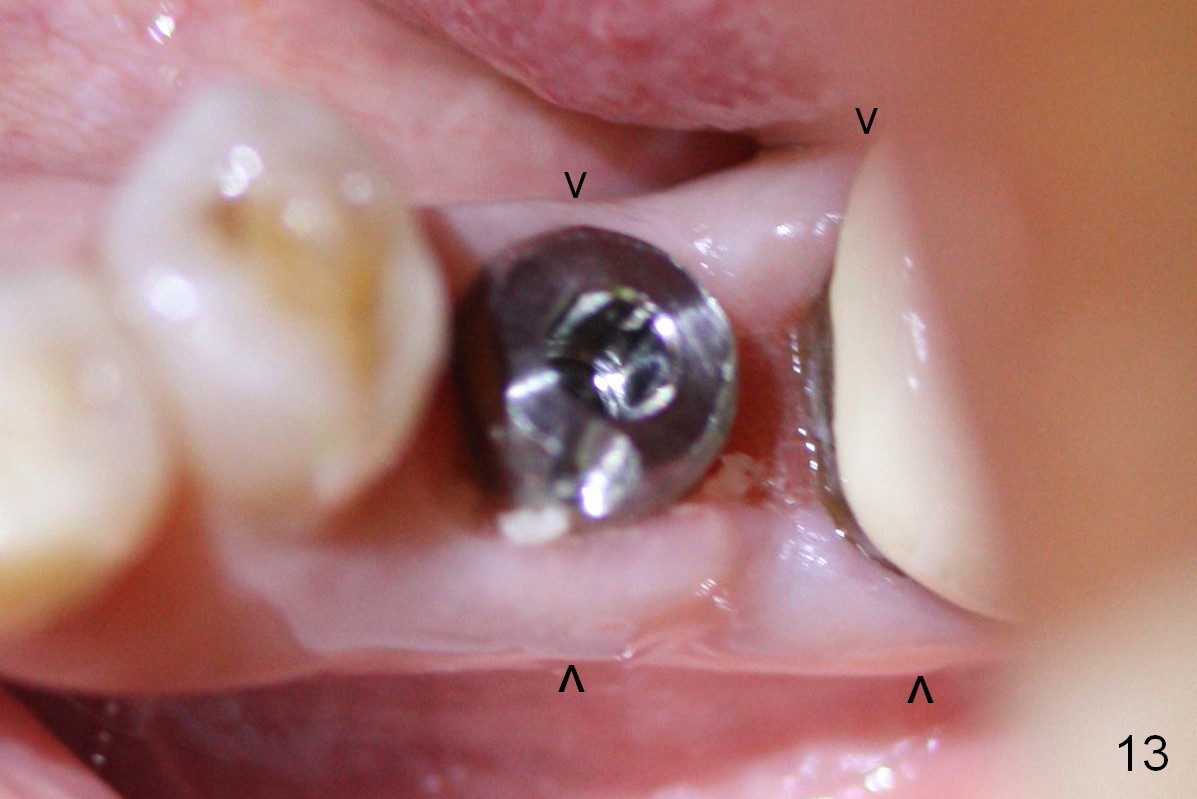

The patient returns for provisional recementation 1.5 months postop. The gingiva remains infection free (Fig.12), but the socket at the implant site has shrunk as compared to the 2nd molar site (Fig.13 arrowheads). Therefore, an implant should be placed before the socket shrinks post extraction, especially with preop lesion. Socket preservation does not prevent socket collapse. The implant is the best framework (tenting) for bone regrowth.